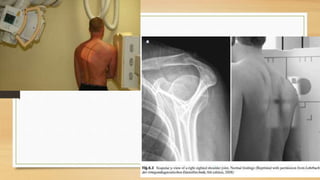

1. RADIOGRAFIA: SERIE TRAUMATICA: AP

EXAMENES DIAGNOSTICOS 1. RADIOGRAFIA:SERIE TRAUMATICA: AP CORREGIDA, ESCAPULAR EN Y Y AXILA 2. TAC 3D